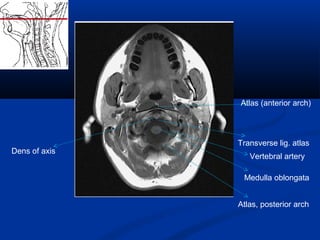

Atlas (anterior arch)

Transverse lig. atlas

Dens of axis

Medulla oblongata

Vertebral artery

Atlas, posterior arch